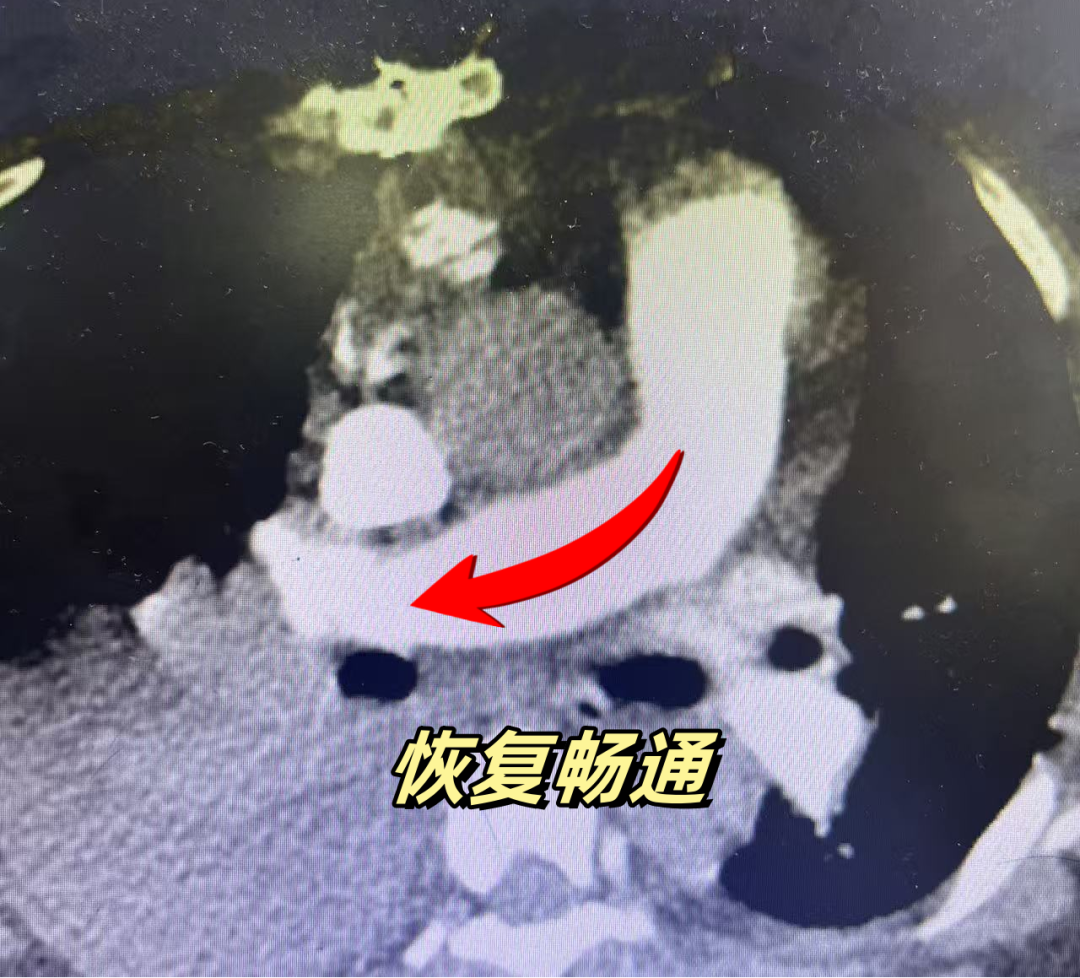

胸心外科团队专家黄继江主任凭借丰富的临床经验和精湛的手术技艺,在高清手术视野下,精准切开肺动脉血管壁,小心翼翼地将堵塞在右主肺动脉内的大块血栓完整取出,同时清理左肺动脉内的部分栓子。整个手术过程中,手术团队、麻醉团队、体外循环团队、重症医学团队全程坚守岗位,密切配合、无缝衔接,每一个操作都精准细致、一丝不苟,历经数小时的紧张奋战,手术终于顺利完成,成功为张女士打通了堵塞的“生命通道”。

劫后余生:科普护航远离栓塞风险